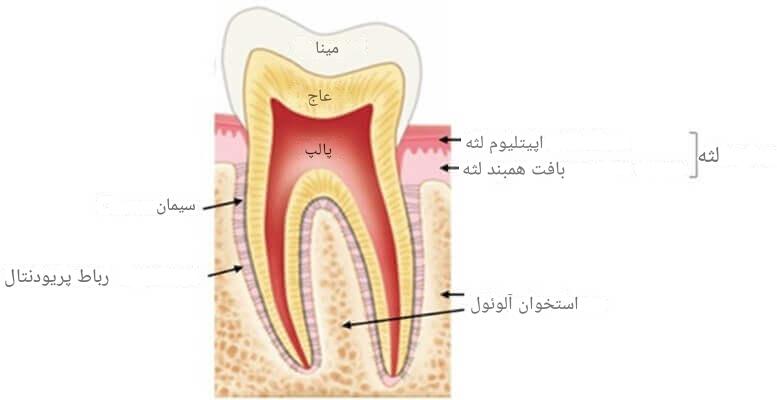

منظور از بیولوژی حرکت دندان در ارتودنسی مطالعه و درک فرآیندهایی است که در طول درمان ارتودنسی در پاسخ به نیروهای مکانیکی وارد شده به دندانها رخ میدهند. زمانی که نیرو به دندانها وارد میشود، تغییرات بیولوژیکی پیچیدهای در بافتهای مختلف دهان رخ میدهد. حرکت دندانها در اثر نیروی وارد شده توسط دستگاههای ارتودنسی، همچون بریسها، منجر به تغییرات در لیگامان پریودنتال، استخوان فک و بافتهای نرم لثه میشود. این تغییرات بیولوژیکی شامل فشرده شدن و کشیده شدن لیگامانها، تحلیل و بازسازی استخوان فک و تغییر در ساختار لثه است که بهتدریج موجب جابهجایی دندانها در جهتهای مختلف میشود. متخصصان با شناخت دقیق این روند، بیماران خود را مؤثرتر و با عوارض کمتری درمان میکنند. در این مقاله میخواهیم فرآیند بیولوژیکی حرکت دندان در ارتودنسی و تأثیر نیروهای مکانیکی بر بازسازی استخوان و بافتهای اطراف دندان را بررسی کنیم.

فرآیند بیولوژی حرکت دندان در ارتودنسی با اعمال نیرویی خفیف اما مداوم از سوی ابزارهای ارتودنسی آغاز میشود. این نیرو باعث میشود دندان به یک سمت حرکت کند و همین موضوع منجر به ایجاد دو ناحیهی متمایز در اطراف آن میشود: ناحیهی فشار (سمت حرکت دندان) و ناحیهی کشش (سمت مقابل). ساختاری به نام لیگامان پریودنتال (رباط نگهدارنده بین ریشه دندان و استخوان فک) مستقیماً تحت تأثیر این تغییر قرار میگیرد و به صورت فشرده یا کشیده درمیآید.

لیگامان پریودنتال و اتفاقات بیولوژیکی طی درمان ارتودنسی

پس از اعمال نیرو، یکی از نخستین ساختارهایی که دچار واکنشهای بیولوژی حرکت دندان در ارتودنسی میشود لیگامان پریودنتال (PDL) است. این رباط نازک اما حیاتی، مانند بالشتکی الاستیک، دندان را به استخوان فک متصل میکند و در جذب فشارهای جویدن و حرکت نقش دارد. زمانی که نیروی ارتودنسی اعمال میشود، این رباط دیگر فقط یک جذبکننده فشار نیست؛ بلکه به محرک اصلی تغییرات بافتی تبدیل میشود.